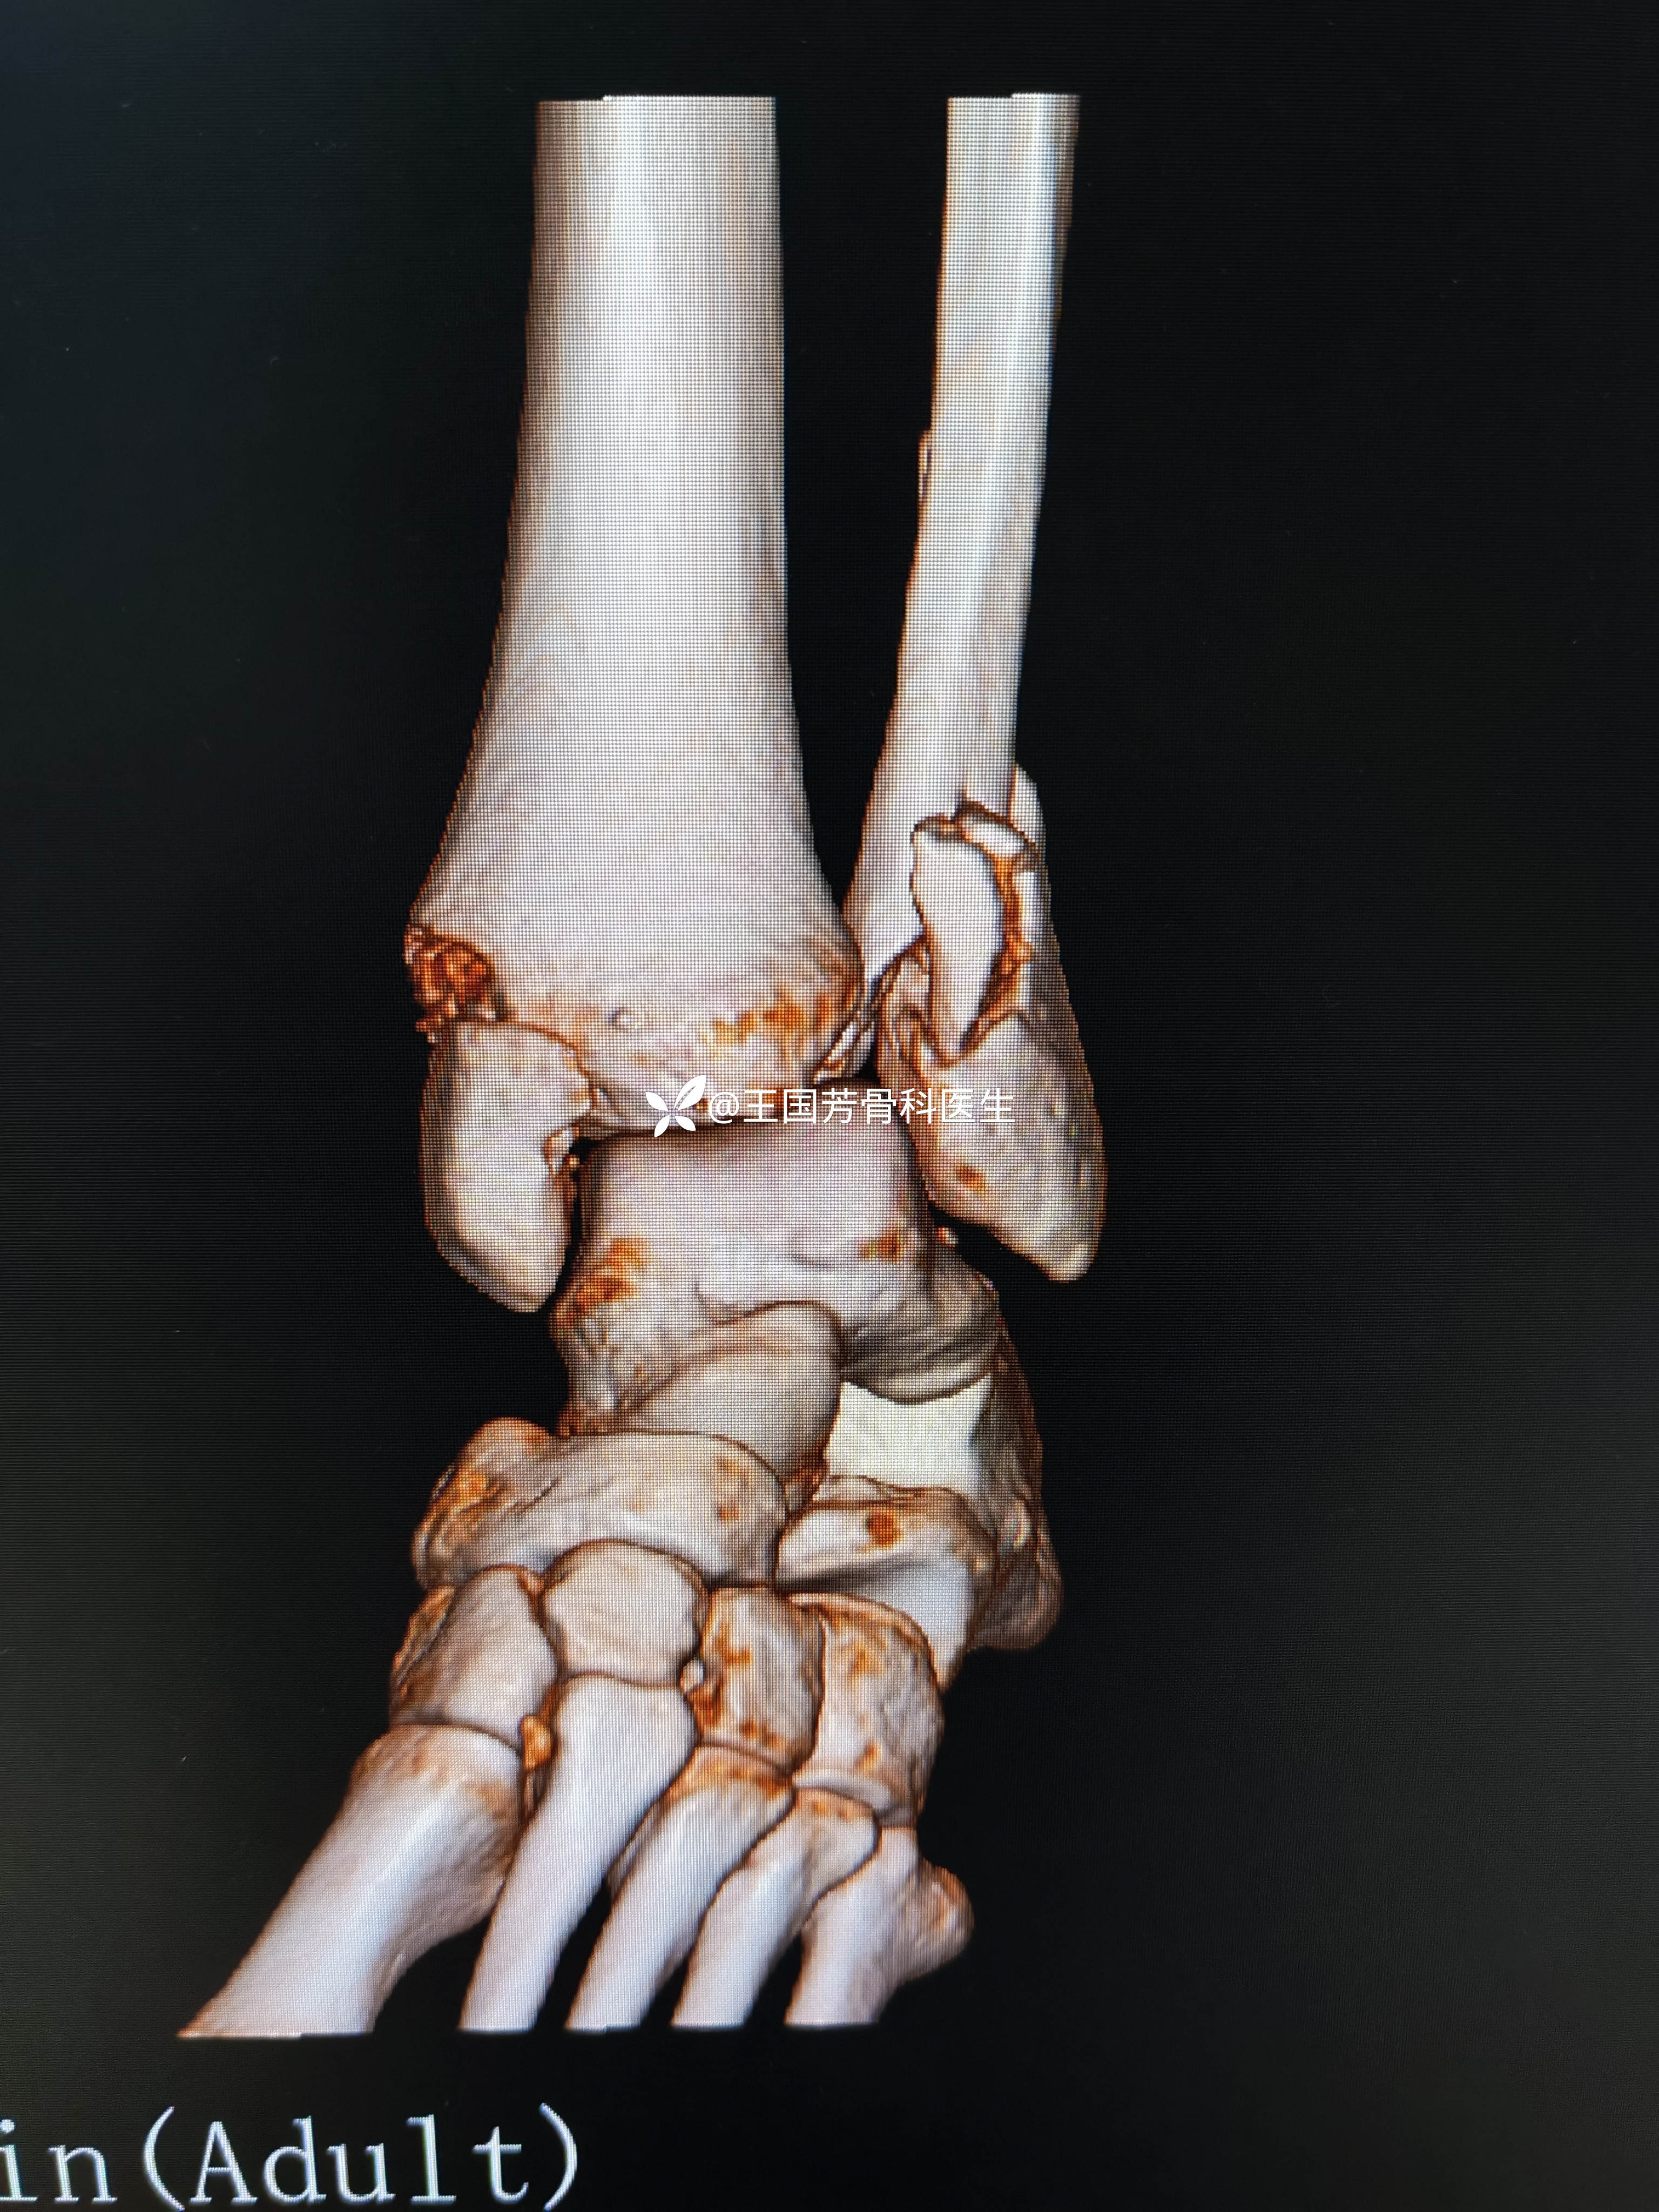

“被迫做的急诊手术”三踝骨折一例

男,27岁,摔伤致左踝肿痛8小时。

8小时前,下楼梯时踩空致摔倒,致左踝部肿痛伴活动受限。急诊于当地医院,检查后,需消肿后手术。家人商量后,到我院咨询,要求急诊手术。转我院,诊断:左三踝粉碎性骨折。收入院,会诊:建议消肿后手术治疗。但家人及患者强烈要求立既手术。否则转院。再次会诊,同意急诊手术。

此病例为旋后外旋

AO分型:C2.3型